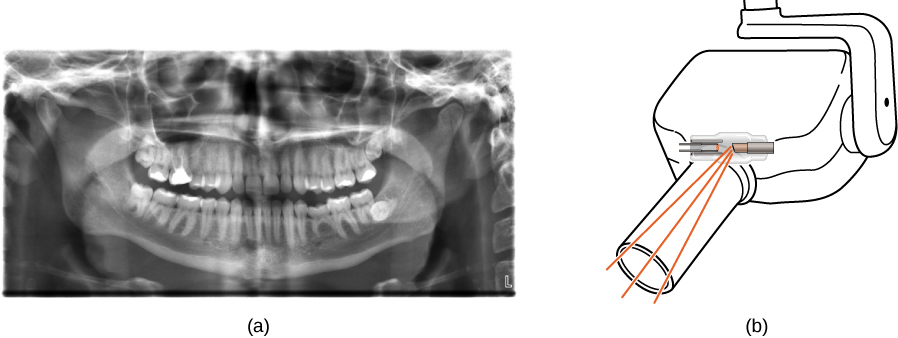

X-rays have many applications, such as in medical diagnostics (Figure 8.25), inspection of luggage at airports (Figure 8.26), and even detection of cracks in crucial aircraft components. The most common X-ray images are due to shadows. Because X-ray photons have high energy, they penetrate materials that are opaque to visible light. The more energy an X-ray photon has, the more material it penetrates. The depth of penetration is related to the density of the material, as well as to the energy of the photon. The denser the material, the fewer X-ray photons get through and the darker the shadow. X-rays are effective at identifying bone breaks and tumors; however, overexposure to X-rays can damage cells in biological organisms.

Figure (a) shows an X-ray image of front view of the jaw, especially the teeth. Figure (b) shows a drawing of an dental x ray machine.

Figure 8.25 (a) An X-ray image of a person’s teeth. (b) A typical X-ray machine in a dentist’s office produces relatively low-energy radiation to minimize patient exposure. (credit a: modification of work by “Dmitry G”/Wikimedia Commons)